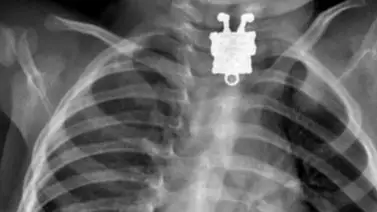

La canción de la popular serie animada Bob Esponja dice que este vive un una piña debajo del mar, pero un llavero de este personaje fue encontrado en el cuello de un menor de 16 meses de edad, gracias a los rayos X.

Sobre los rayos X, Ageely dijo al medio Live Science que “se sorprendió por los detalles visibles”. “Se pueden ver sus pecas, sus zapatos y sus dedos”, dijo.

Afortunadamente, el pequeño juguete fue retirado del esófago del pequeño sin ningún tipo de complicaciones; sin embargo, siempre es preferible hacer caso a las recomendaciones y no dejar que los niños menores de tres años manipulen juguetes pequeños, ya que pueden ser tragados y hasta inhalados.